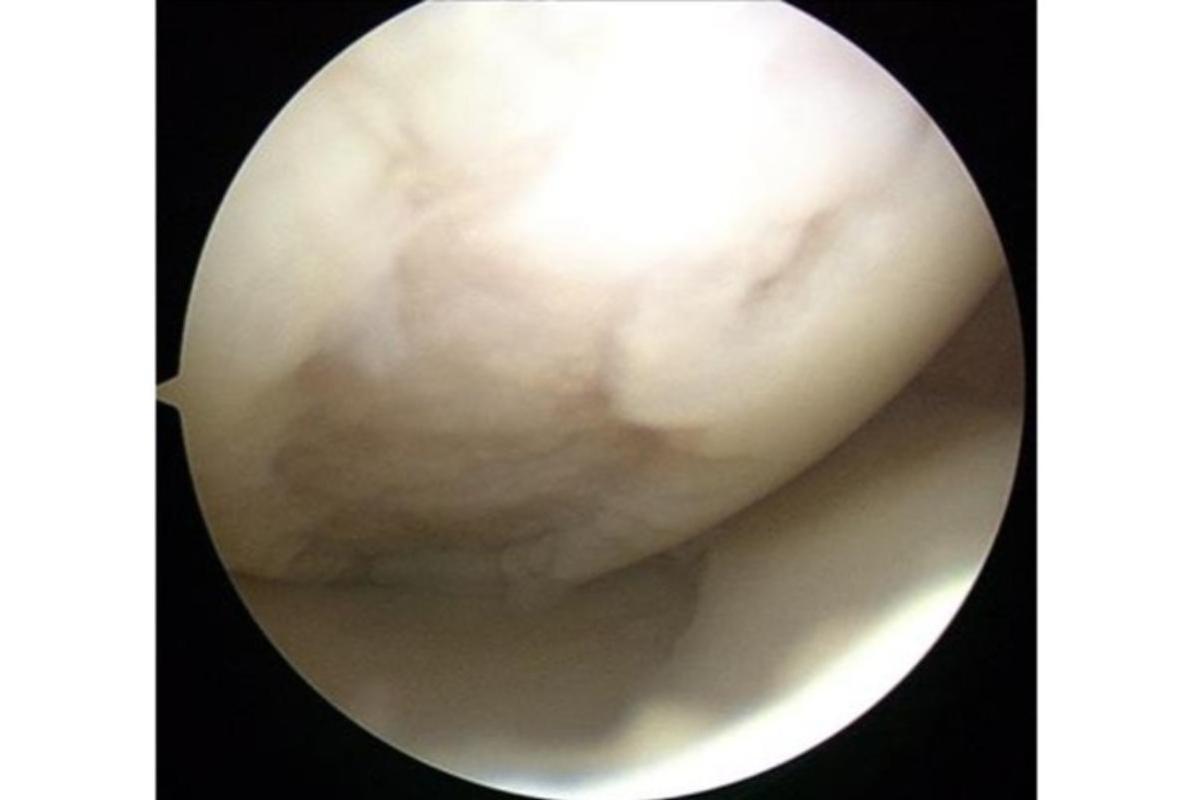

損傷した膝軟骨の内視鏡画像